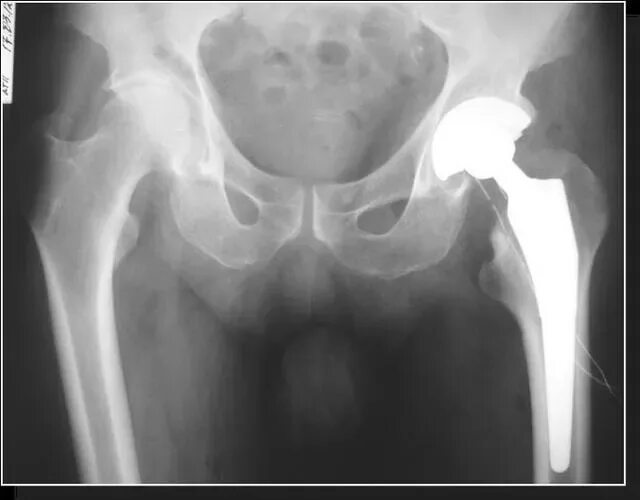

Артроз тазобедренного сустава симптомы у мужчин